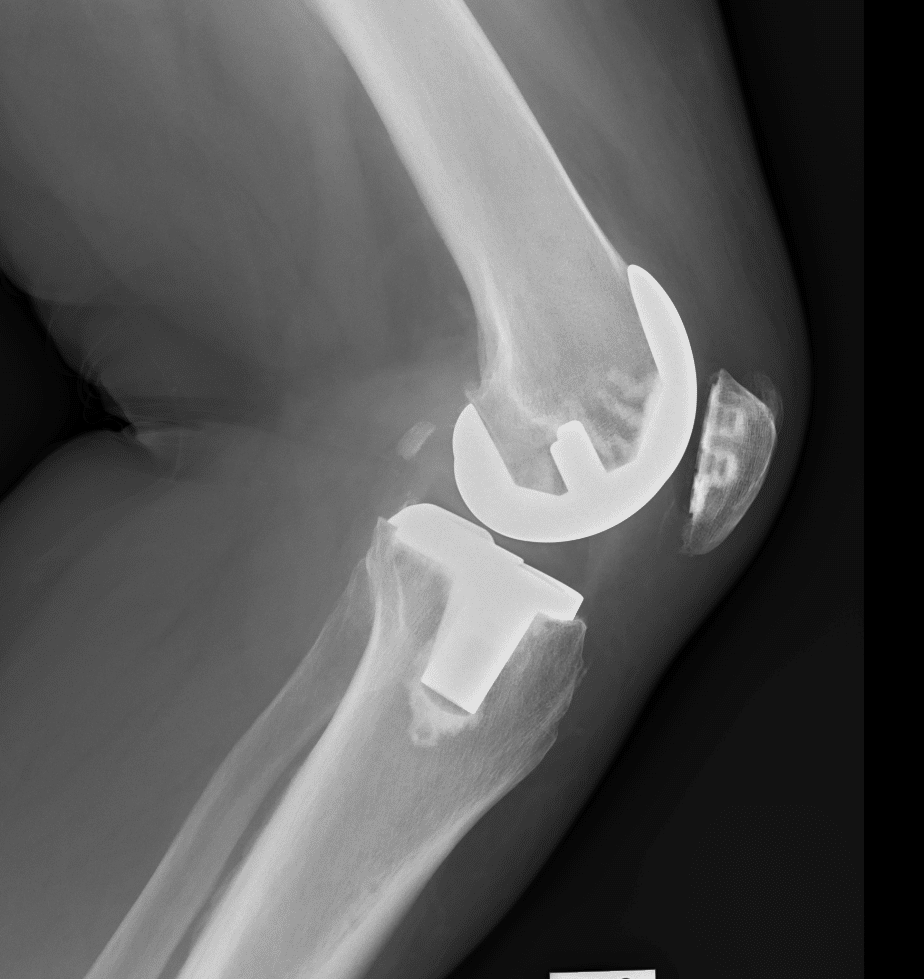

Knee Replacement is a common orthopaedic procedure and is used primarily to treat knee arthritis and cartilage damage of all causes. Knee replacement surgery is now more technologically advanced and utilities assistance from computer navigation and robotic interventions. The Surgery involves removal of arthritic bone surfaces and replacement with metal and plastic leading to improved pain and function in the large majority of patients.

Damage to the knee that is likely to benefit from Knee Replacement surgery is usually diagnosed both clinically, with pain, stiffness and swelling of the knee, and with x-rays. Occasionally an MRI may assist in the diagnosis of Knee Arthritis.

The goals of knee replacement surgery are to reduce pain, increase mobility and function and to restore alignment to limbs with preoperative deformity.